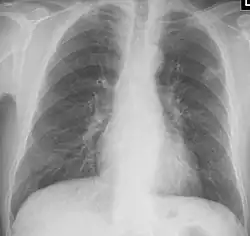

Speziell im Fall eines 3D-Datensatzes werden häufig Schnittbilder oder Schnittbildserien des Körpers errechnet. Die Orientierung der Schnittbildebene und die Position sind dabei meist frei wählbar. Im Gegensatz zu einem Projektionsverfahren wie der Durchstrahlung eines Körpers können so gezielt Details oberhalb oder unterhalb der interessierenden Schicht ausgeblendet werden. Im unteren Beispiel wurde durch die Technik der Schnittebene die störende Information der Rippen entfernt. Teilweise werden für die Diagnose oder Auswertung auch 3D-Rekonstruktionen erstellt, die sich beliebig im Raum orientieren lassen und Anblicke von allen Seiten erlauben.

Projektion (normale Röntgenaufnahme) -

Schnittbild in Körperlängsachse (frontaler Schnitt)